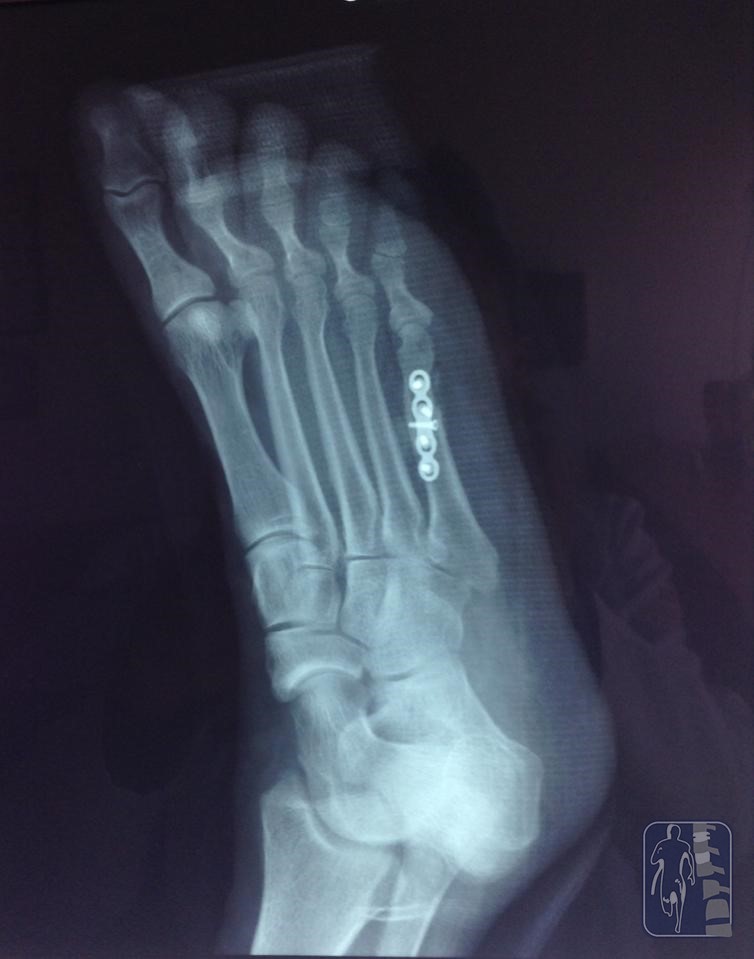

Osteosíntesis de 5o metatarsiano